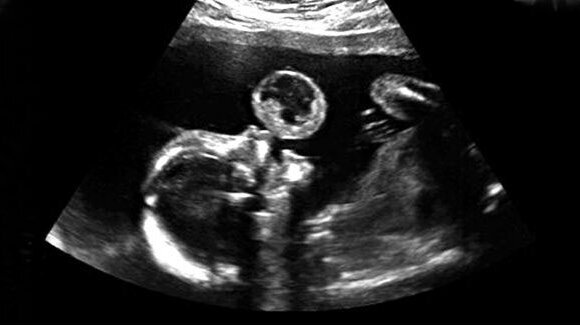

MIAMI – Chirurgen zijn erin geslaagd om voor de eerste keer een orale tumor bij een foetus te verwijderen. Dat werd eind juni bekend gemaakt tijdens een persconferentie van het Jackson Memorial Hospital. Het geopereerde kind is inmiddels twintig maanden oud en heeft, op een klein litteken bij de mond na, niets overgehouden aan de operatie.

De tumor, een teratoom, werd ontdekt tijdens een routine echo-onderzoek in de twintigste week van de zwangerschap van een 37-jarige vrouw. Ruben Quintero, hoogleraar Obstetrie en Gynaecologie, en Eftichia Konopoulis, assistent-hoogleraar Obstetrie en Gynaecologie, verwijderden de tumor onder lokale anesthesie met een endoscoop en met behulp van echo apparatuur en een laser. De operatie duurde 68 minuten en noch de moeder noch de foetus hebben complicaties aan de operatie overgehouden. Vijf maanden na de operatie beviel de vrouw spontaan van een gezond meisje.

Volgens de chirurgen overleeft gemiddeld tussen de 30% en 40% van de foetussen met een teratoom; veel baby’s sterven doordat hun luchtwegen geblokkeerd worden. Een baby met een teratoom kan de bevalling alleen overleven met een keizersnede en als daarna gelijk een tracheotomie wordt geplaatst zodat de baby kan ademhalen. Na de bevalling moet de baby vervolgens meerdere operaties ondergaan.

Door de tumor tijdig bij de foetus te verwijderen, kan voorkomen worden dat de tumor groeit en dat het gezicht misvormd raakt. Ook wordt het risico op een teveel aan vruchtwater, oedeem en een doodgeboren kind verkleind.